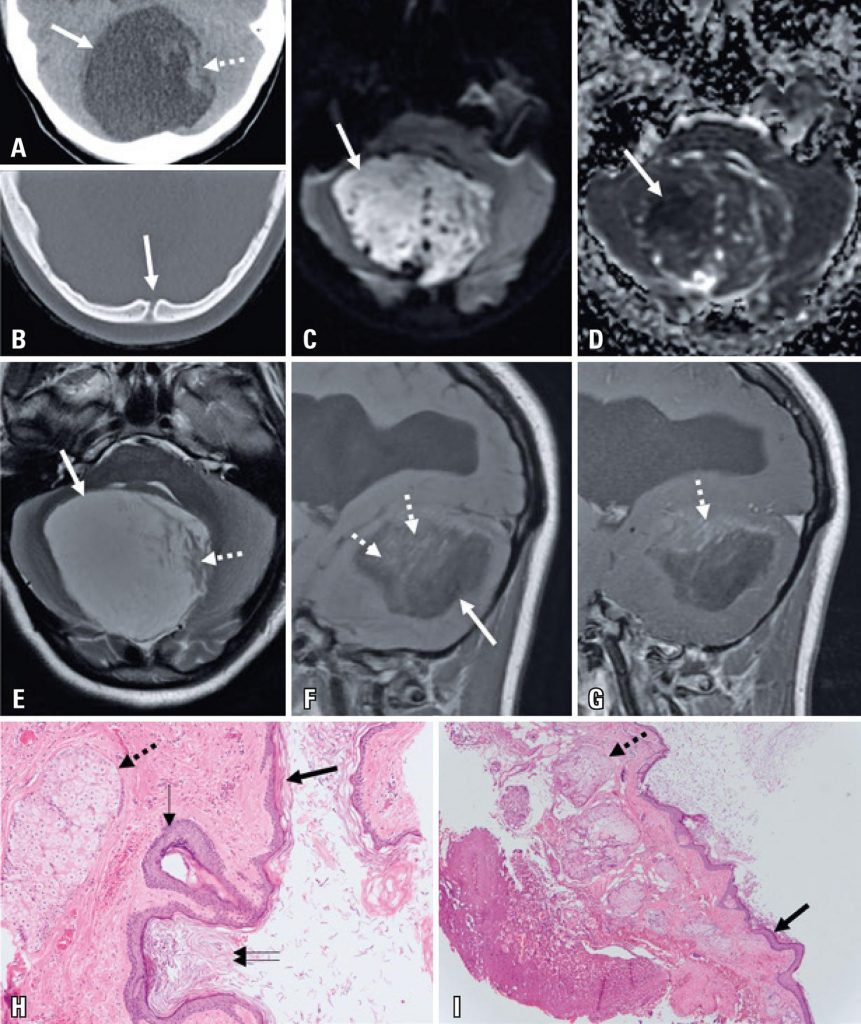

Paciente do sexo feminino, 15 anos, com histórico de 6 meses de tremor progressivo na mão direta com disfunção funcional, agravada por histórico de 1 mês de ataque episódico. A paciente foi submetida a rastreamento por tomografia computadorizada, que revelou lesão expandida da fossa posterior com densidade similar a de fluido raquimedular e descontinuidade óssea na linha mediana ( ; janela de tecido mole não demonstrada). O exame de imagem por ressonância magnética (RM) ( ) foi realizado após internação hospitalar, revelando lesão expandida na fossa posterior, com predominância de hiperintensidade T2, hipointensidade T1 e áreas lineares com redução de difusão de água. As imagens supratentoriais reveleram sinais de hidrocéfalo crônico. A paciente foi submetida à cirurgia, na qual se observou lesão capsulada extra-axial com substância branca contendo apêndices cutâneos, sendo confirmado o diagnóstico de cisto dermoide na histologia ( ).